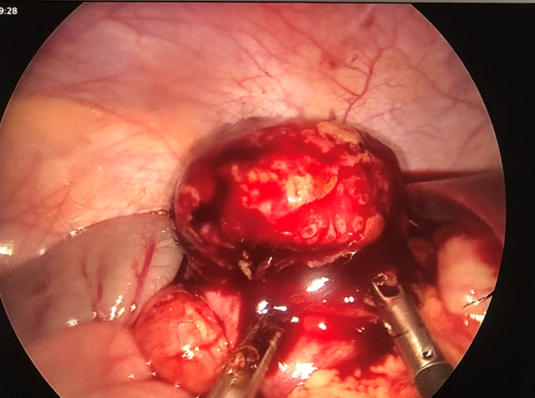

đòi hỏi phẫu thuật viên phải có kinh nghiệm. Sau khi mở manh tràng, bộc lộ khối

u, các bác sĩ đã tiến hành cắt u bằng dụng cụ nội soi, khối u không có cuống,

đường kính 3cm (Hình 3), phần tiếp giáp với thành manh tràng rộng, nguy cơ thủng

manh tràng trong phẫu thuật cao. Tuy nhiên kíp mổ đã cắt thành công toàn bộ khối

u an toàn và gửi u làm xét nghiệm mô bệnh học.

Hình

3: Khối u manh tràng được bộc lộ qua chỗ mở manh tràng bằng nội soi